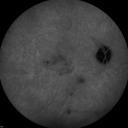

Cuticular Drusen (Basal Laminar Drusen) and Bilateral Chronic Subfoveal Fluid (Serous Retinal Detachment) unresponsive to monthly Avastin - Infrared OS607 views66-year-old man with bilateral subfoveal fluid unresponsive to one year of monthly avastin therapy.

OD 20/160, Pinhole 20/80. OS 20/63, Pinhole 20/50. OCT scan shows subretinal fluid with normal choroidal thickness. Fluorescein angiogram shows cuticular/basal laminar drusen. ICG shows no foci of choriocapillaris leakage.